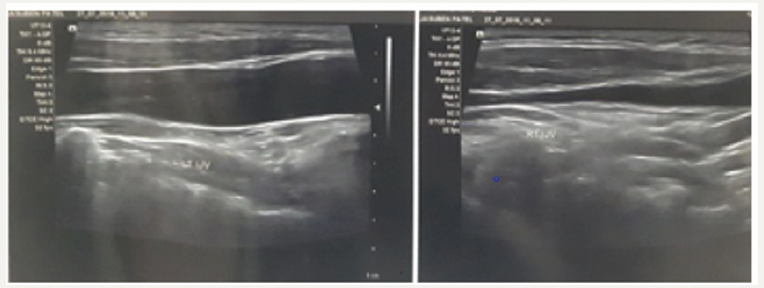

In adults, left sided jugular phlebectasia was described by Tohru Tanigawa, from Japan, in a 74-year-old elderly female [11]. Right sided lesions in adults, which are more common, were reported by Ozdemir [12], who reported a case of right EJP with duplication of the internal jugular vein in 2004, Pandey [13] reported a surgically managed case in a 24-year-old male in 2008 and in 2014, Matsunaga k [14], who noticed an incidental finding of a right sided EJP in an 81-year-old man undergoing surgery for hernia. In this case report we try to highlight the diagnosis of an external jugular venous phlebectasia on the left side, in an adult. The internal jugular vein is also dilated which was only detected by the ultrasonography report. This may lead to complications like hoarseness and difficulty in swallowing, if enlarged. Thus, the diagnosis of jugular phlebectasia should be considered, though rare, in all cases of left venous dilatation. Unnecessary investigations for cardiovascular diseases also may be avoided if diagnosed early. A good clinical examination and a USG and a Doppler can diagnose this condition accurately and help differentiate it from other neck swellings (Figure 3). A raised jugular venous pressure may also appear as the similar presentation; however, it is more on the right side, associated with cardiac failure and pulsations may be seen only on supine position at a 45-degree angle. With this case report we would like to increase the awareness of this condition if diagnosed correctly when present, will avoid unnecessary investigations and appropriate management can be undertaken swiftly.

Figure 3:USG showing increased prominence of the internal jugular vein.